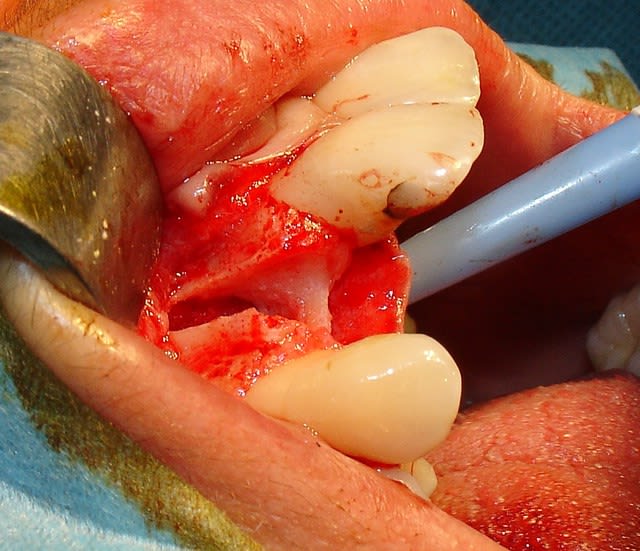

Tiens pour agrémenter! Cet Après midi une extraction implantation. Je n'ai pas oser la mise en charge immédiate si certains l'aurait fait lachez vous.

J'ai fait sauter la table vestibulaire exprès car je ne vois pas comment elle aurait pu etre vascularisée et à part me faire un séquestre osseux et des ennuis j'ai reconstruis.

Regardez les images;

Si certains n'auraient pas extrait argumentez pour traiter en palatin et la felure englobé par le granulome m^me si ce n'est pas mis en évidence sur le scan.

En plus vous voyez le nouvel implant Leone et son indication majeure, c'est vrai que sa mise en place est super aisée, surtout comme celà en palatin.